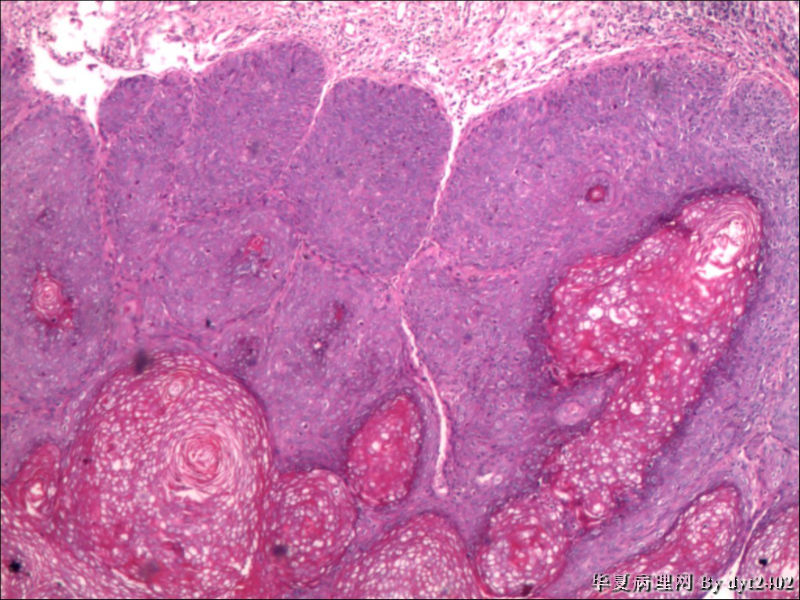

这样的外阴病变 发个原位癌是否合适?

• 这样的外阴病变 发个原位癌是否合适?图2

图2

原位癌够了,不排除其他地方有浸润。

似乎有浸润了

VIN III,做个银染或者标个免疫组化看一下基底膜是否完整。

看上去好像还完整 只是经常看见图5 那样结构的就觉得可能还有更重病变

VIN III